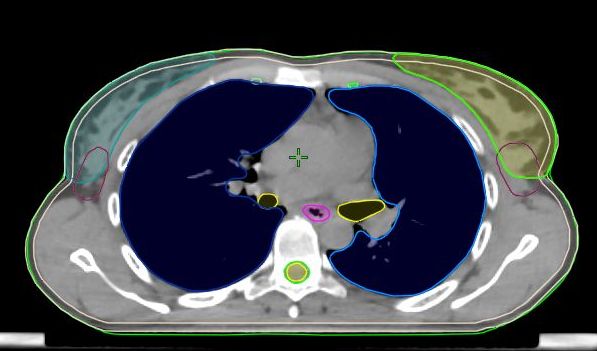

Ennek eléréséhez elengedhetetlen a pontos besugárzástervezés, amelynek alapja a kezelendő céltérfogat (daganat) és a környező kockázati szervek (pl. tüdő, szív, gerincvelő) pontos meghatározása a képalkotó felvételeken (CT, MRI), amit kontúrozásnak (körberajzolásnak) hívnak. Ez a folyamat hagyományosan manuálisan, kézi rajzolással történik, ami időigényes és operátorfüggő lehet.

Hogyan működnek? Ezek a szoftvereket nagy mennyiségű, szakorvosok által manuálisan kontúrozott képalkotó adatokkal (CT, MRI felvételek) tanítják. A betanítás során az MI modell megtanulja azonosítani az anatómai struktúrák jellegzetességeit és határait, majd ezt a tudást alkalmazza az új, ismeretlen felvételeken a kontúrok automatikus létrehozásához.

Vizuális összehasonlítás

A kontúrsorozatokat szemrevételezéssel szeletenként össze lehet hasonlítani tetszőleges orientációjó képmegjelenítéseken.Kvantitatív összehasonlítás térfogati és felületi mérőszámokkal